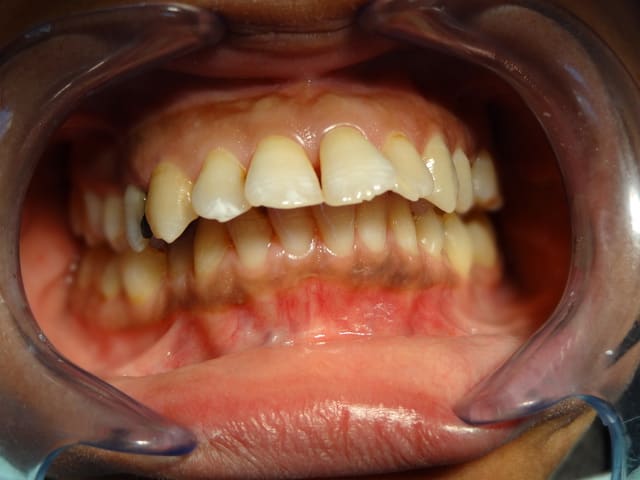

Bonjour,c'est une patiente de 36 ans qui consulte pour un souci esthétique " dents antero sup trop en avant" , elle refuse toute proposition de chirurgie, qu'est ce que vous proposez comme plan de traitement ?

Qu'elle commence par soigner ses caries..., après c'est de la cuisine d'ortho.

tout va bien sur la 15? pas une petite ENORME carie?

Pffft, la 23 ?

+1 pour les caries multiples / ortho....

dr_0le - bagheerra, ceramique : la patiente a été prise en charge pour la mise en etat de la cavité bucale, parlons maintenent orthodontie

Pas de problem paro a envisager dans le futur pour mois, le niveaux d'os est excellent pour une patient de 36 ans.

Sinon le cas me semble assez simple soigner les carries et traitement classique avec deux options